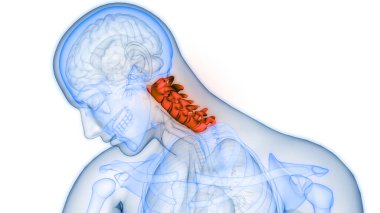

The arterial blood supply to the neck (carotids and vertebral arteries).

İnsanBaşıkanİlaçyüzboğazıBoyunresim çalışmasıprofilNormalbeyinarterkarotidKan damarıKan dolaşımıİnsan AnatomisiSerebral kan dolaşımıvaskülarizasyonsubclavian arteryortak Karotis arterbrachiocephalic Arteryel gövdeVertebral arterfacial arteryserebral artercervical arterytemporal arterydahili şah damarıharici şah damarıdeep cervical arteryBenzer İçerikler